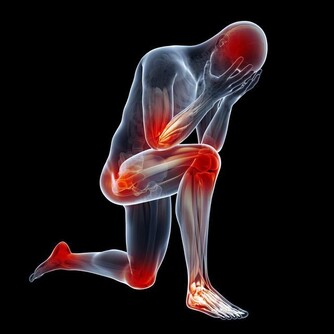

▼一旦你做完這些動作,身體就會像這樣輕盈又暢快喔。